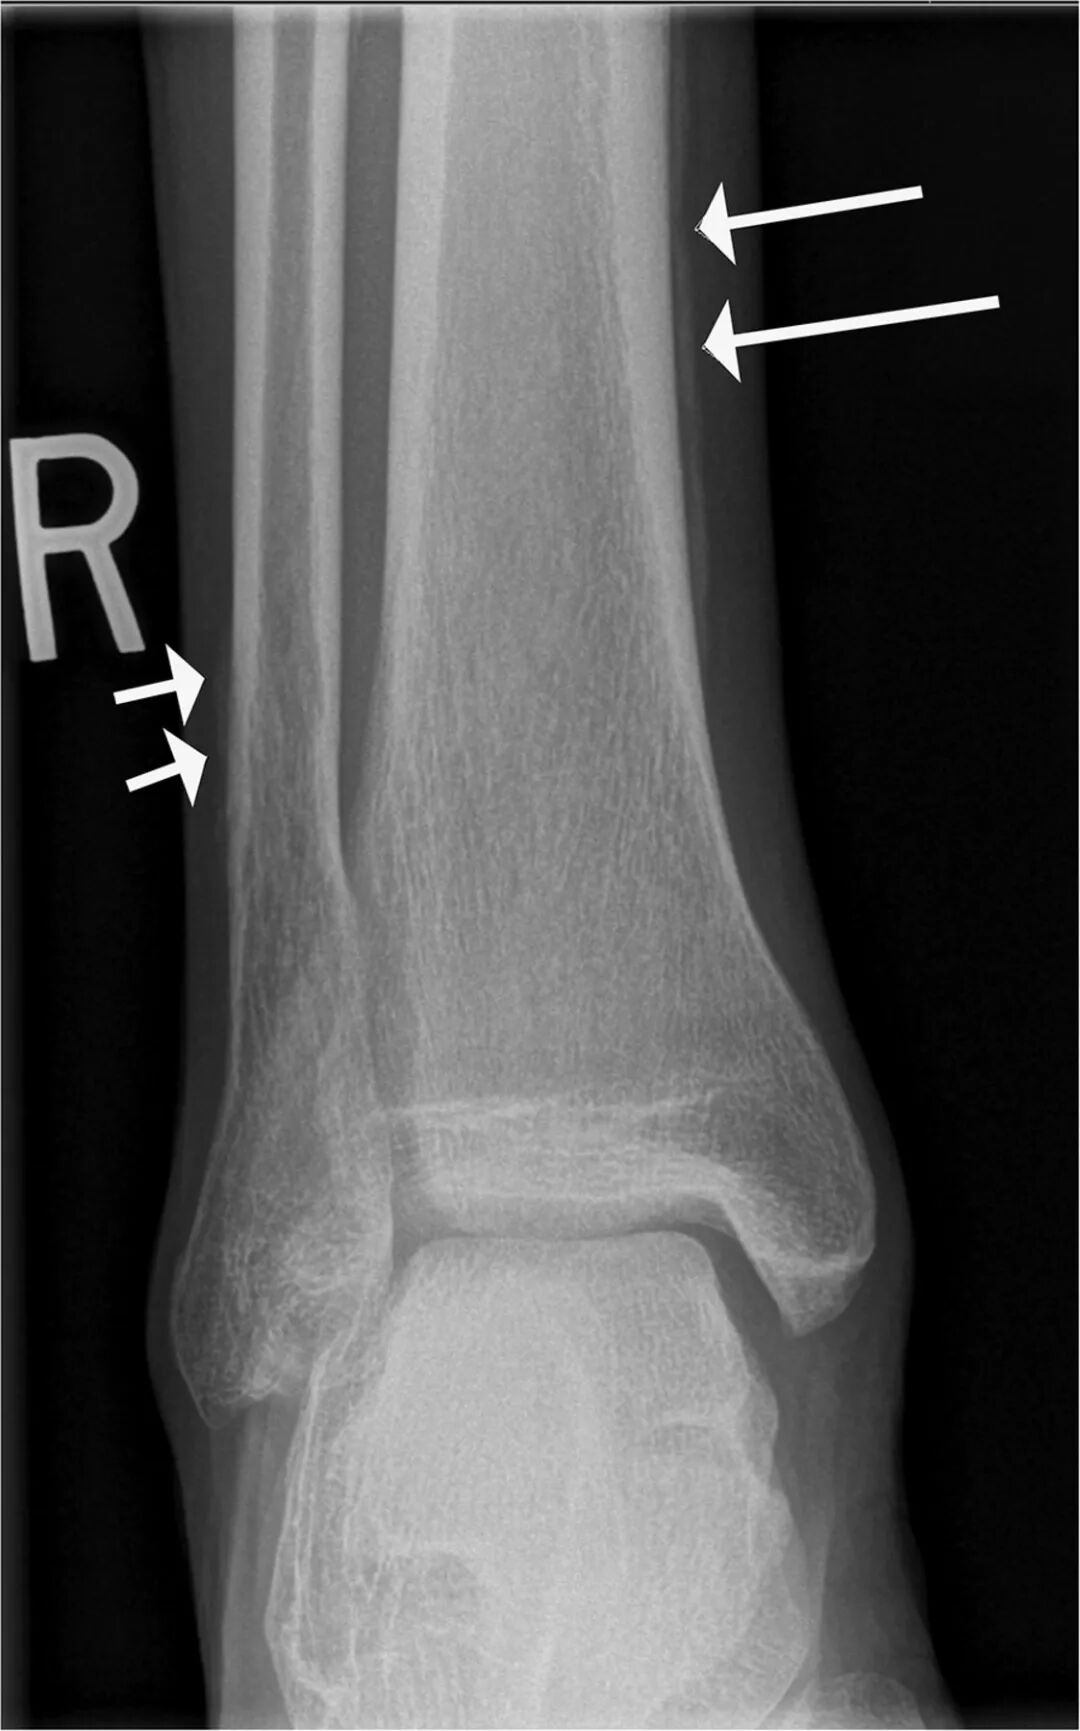

肥大性骨关节病又称Marie-Bamberger综合征,表现为对称性的关节肿痛,以大关节受累最常见,常被误诊为类风湿关节病。本病最常见和最主要的病因是胸腔内疾病,约80%合并肺内疾病,其中2/3为支气管癌,1/5为良性肿瘤。

病骨区软组织有肿胀压痛,以胫腓骨和桡尺骨远端较为显著,严重者可累及股骨、肱骨、掌骨和跖骨等,也有累及膝、踝、腕等大关节。其确诊主要依靠影像学证据,表现为双侧管状骨对称性骨膜增生。增生的骨膜可呈层状、葱皮样或花边样,骨膜新生骨与骨皮质之间多可见一透亮线;关节病变多表现为关节软组织肿胀、关节积液及关节周围骨质疏松等征象。核素骨显像的特征表现为对称性“双轨征”和(或)对称性关节周围放射性浓集。

肥大性骨关节病与大细胞癌、鳞癌、腺癌密切相关,有时是肺癌早期的唯一症状,很大一部分患者被误诊为类风湿性关节炎。

如果患者在骨科就诊发现肥大性骨关节病,临床医生一定要警惕有无肺部疾患可能,不然,等患者有肺部症状后再来检查,可能一切晚矣。